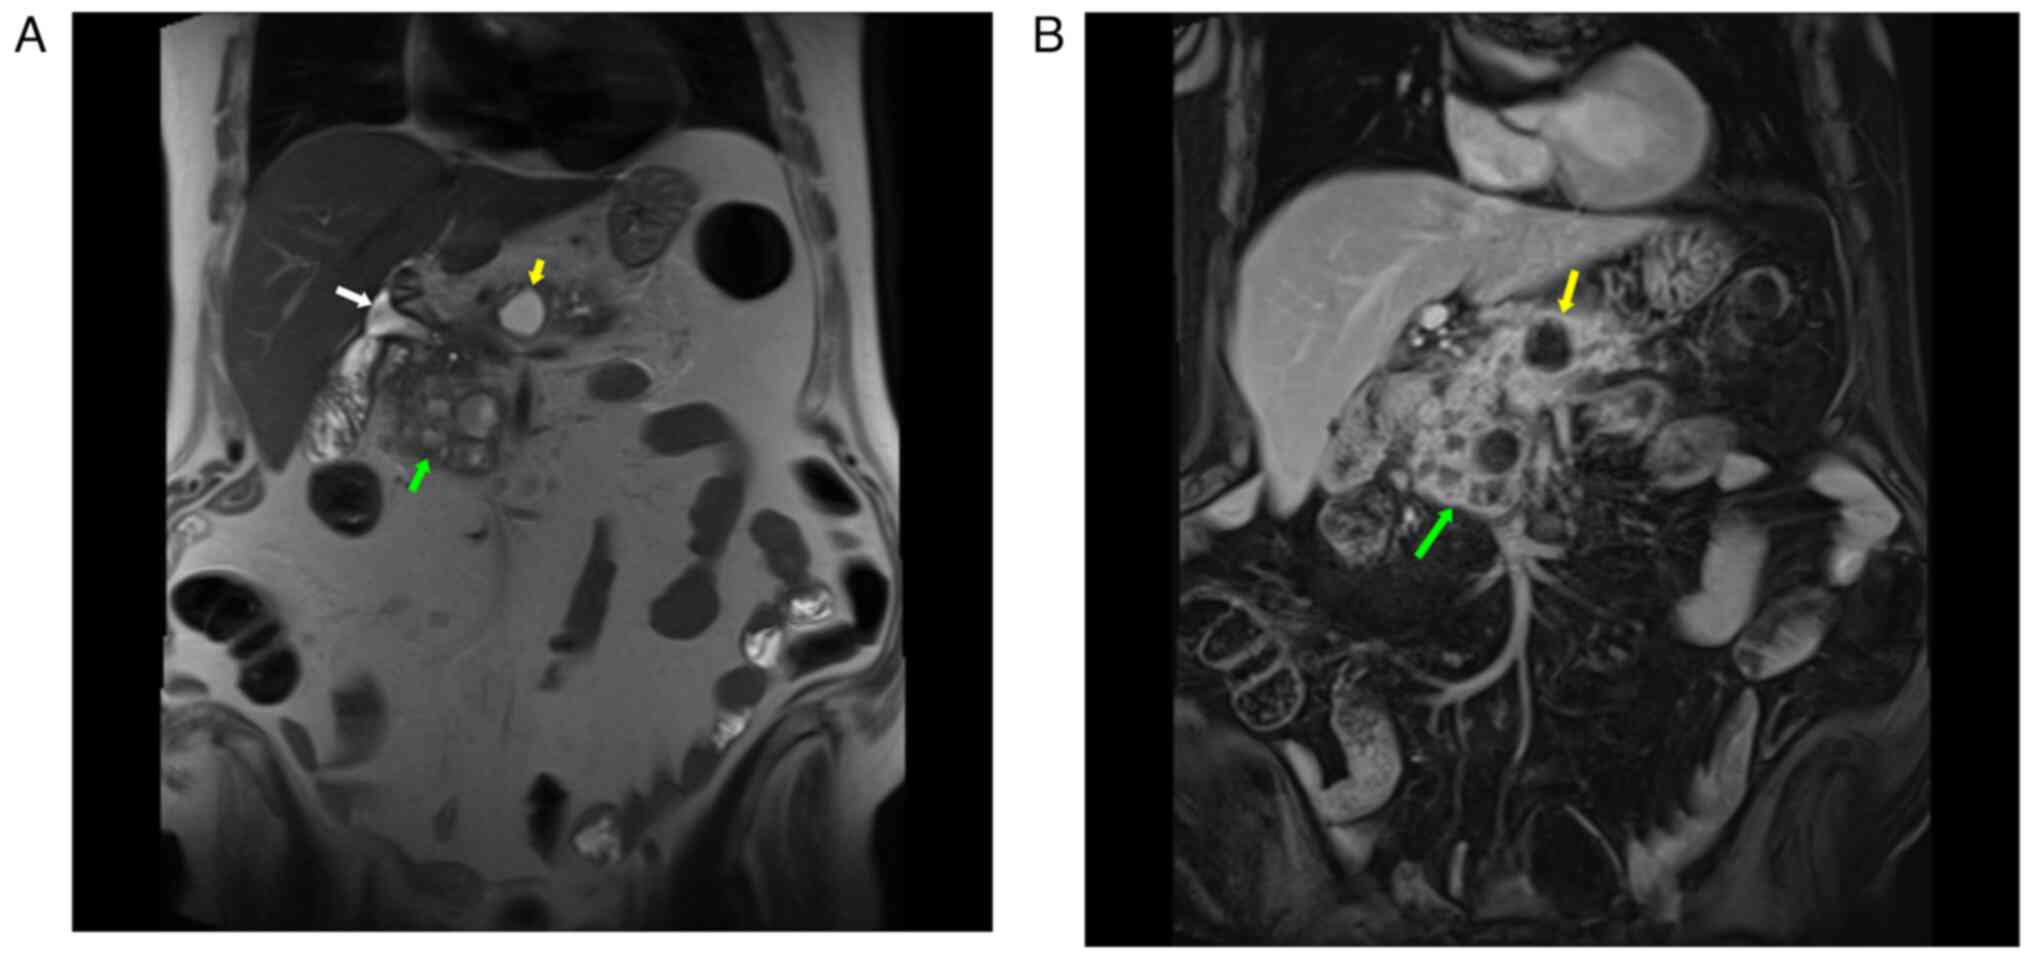

An endoscopic ultrasound (EUS) revealed a cystic

computed tomography (CT) scan confirmed this finding. Magnetic

resonance imaging (MRI) of the abdomen further detailed a

multiloculated cyst situated in the head and uncinate process of

the pancreas, measuring 54x58x51 mm. It had a thick enhancing wall

with multiple thick enhancing septae, diffusion restriction, and no

communication with the pancreatic duct (Fig. 1). At least eight local reactive

lymph nodes were identified (all <7 mm in short-axis diameter).

The lesion adjoined the superior mesenteric vein and portal vein

for a distance of >5 cm; however, there were no signs of

invasion into the gastroduodenal artery, hepatic artery, or

superior mesenteric artery. Another cyst, measuring 20x20 mm, was

observed at the posterior aspect of the pancreatic body, with an

apparent connection to the side branch of the pancreatic duct. The

common bile duct had a diameter of 10 mm, and the main pancreatic

duct was 5 mm, both of which entered the mass region. There were,

additionally, several small pancreatic cysts in the background that

reached out to the spleen. Fine-needle aspiration cytology revealed

a pyogenic inflammatory process with extensive pancreatic fibrosis

and no evidence of malignancy.

by false-positive and false-negative results (17). Various imaging modalities are

useful in the diagnosis of pancreatic cysts, including CT, MRI and

ultrasonography (9). In the case

in the present study, an MRI revealed a multilocular cystic lesion

in the head and the uncinate process of the pancreas with a thick

enhancing wall and multiple thick enhancing septae. EUS and ERCP